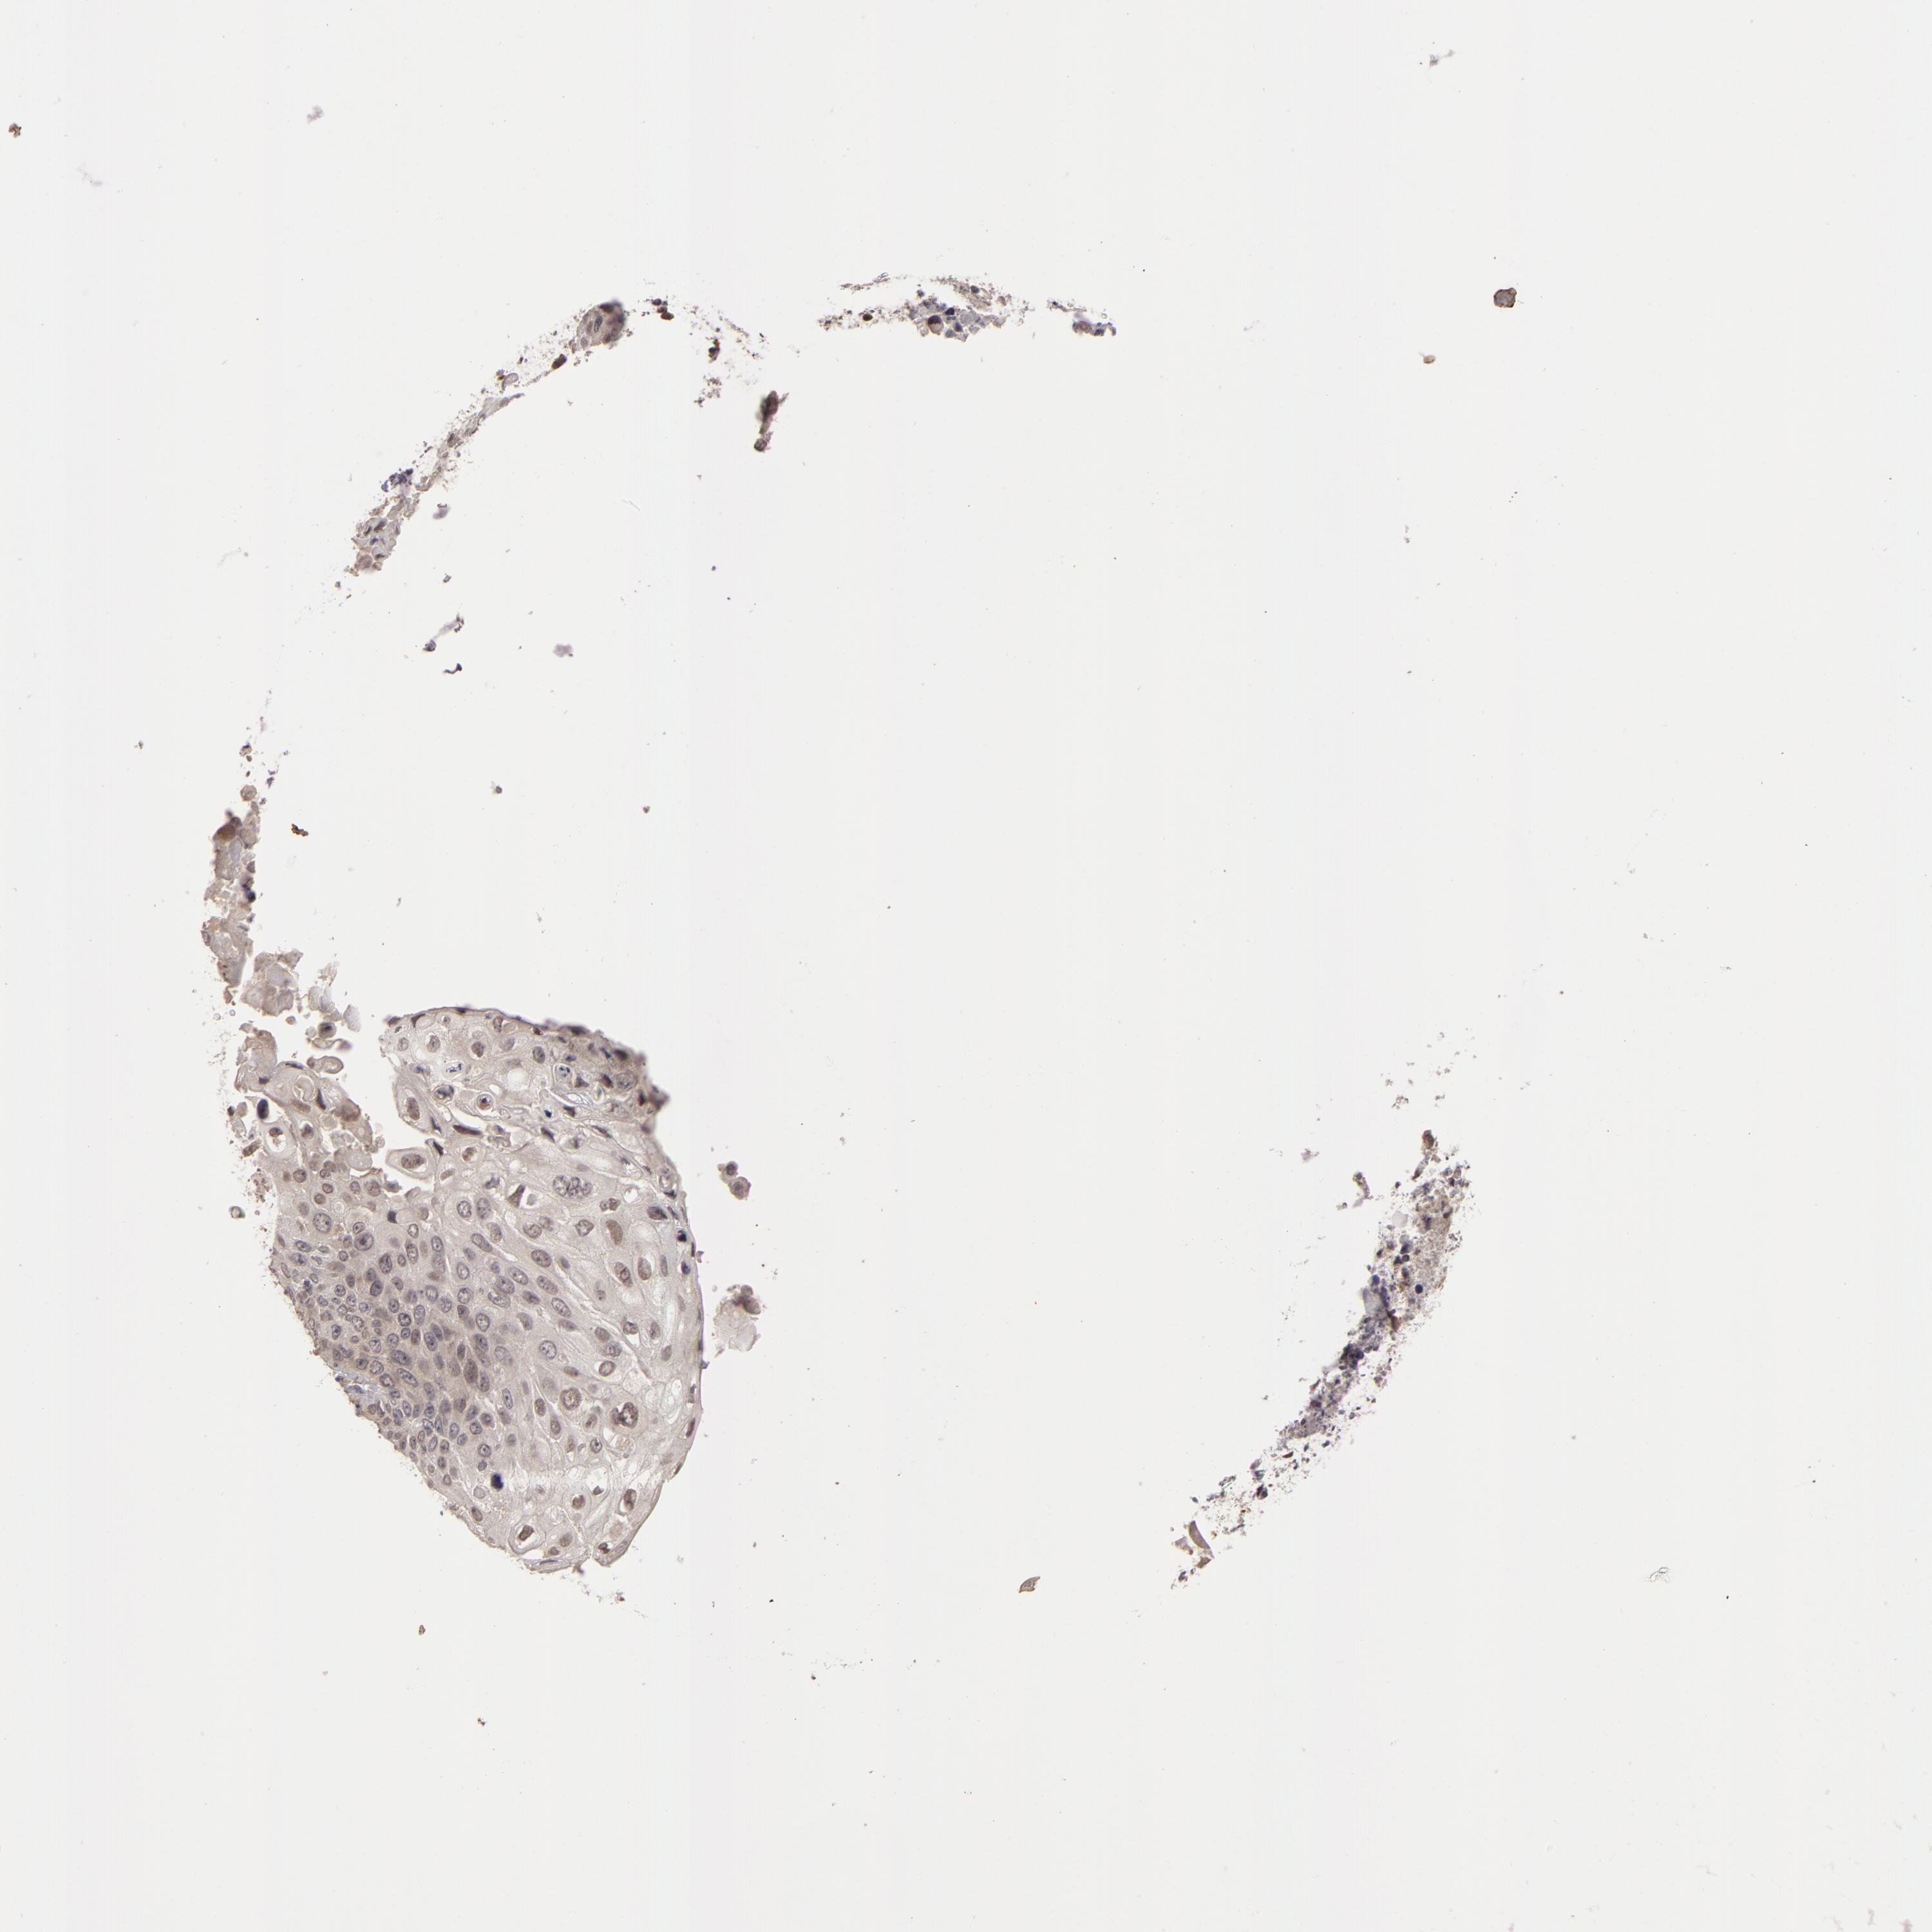

CANCER LUNG CANCER Show tissue menu

LUAD TCGA LUAD VALIDATION LUSC TCGA LUSC VALIDATION PROTEIN LUAD CPTAC PROTEIN LUSC CPTAC PROTEIN EXPRESSION

ANTIBODIES

AND

VALIDATION